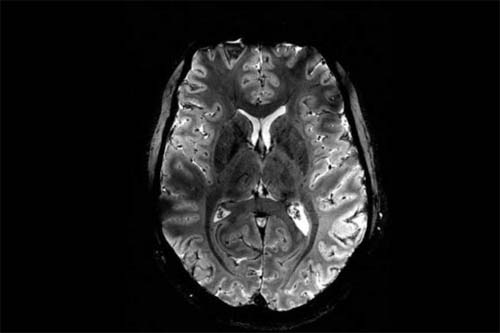

Silenciosa, a doença de Alzheimer se instala no cérebro muito tempo antes de os primeiros sinais de demência se manifestarem. Agora, pesquisadores da Universidade Queen Mary de Londres anunciaram um novo método para prever a neuropatologia com mais de 80% de precisão até nove anos antes do diagnóstico. O resultado sai em minutos, afirmam os cientistas, em um artigo publicado na revista Nature Mental Health.

Liderados por Charles Marshall, os pesquisadores desenvolveram o teste ao analisar exames de ressonância magnética funcional (fMRI) para detectar mudanças na chamada rede de modo padrão do cérebro (DMN). A DMN conecta diversas regiões do cérebro para o desempenho de funções cognitivas e é a primeira a ser afetada pelo Alzheimer.

Foram usados exames de fMRI de mais de 1,1 mil voluntários, cujos registros médicos estão no UK Biobank, o maior banco de dados biomédicos do mundo, com informações de genética e saúde de 500 mil pessoas do Reino Unido. O objetivo era estimar a conectividade efetiva entre 10 regiões do cérebro implicadas no modo padrão.